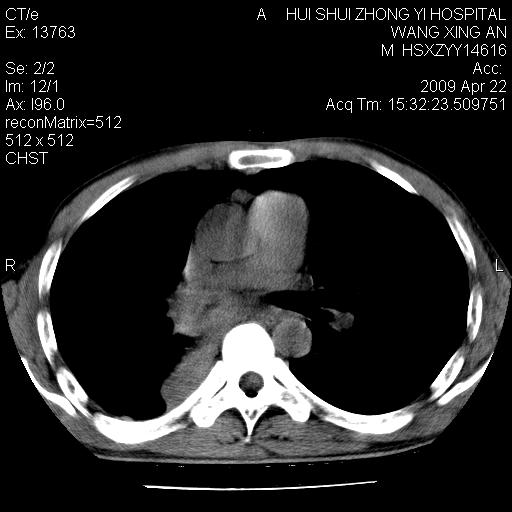

标题: CT19534:患者男、46岁咳嗽、胸痛半月。 [打印本页]

标题: CT19534:患者男、46岁咳嗽、胸痛半月。

1、右下肺中央型肺癌并右肺转移,右肺下叶不张。(右肺有结节影)。

2、右中上肺陈旧性肺结核(因为大多为纤维灶)。

3、右侧胸腔积液。

1、右下肺中央型肺癌并右肺转移,右肺下叶不张。(肿块围绕右肺下叶支气管生长,致管腔闭塞右肺下叶不张;右肺有结节影)。

2、右侧胸腔积液。

3、右中上肺陈旧性肺结核(右肺见纤维化病灶及点状钙化)。

1、右下肺中央型肺癌并右肺转移,右肺中下叶不张。(右肺有结节影)。胸骨转移

1)右肺中间段支气管癌并右肺下叶肺不张。2)右肺上叶、两肺下叶背段感染性病变。3)右侧少量胸腔积液。